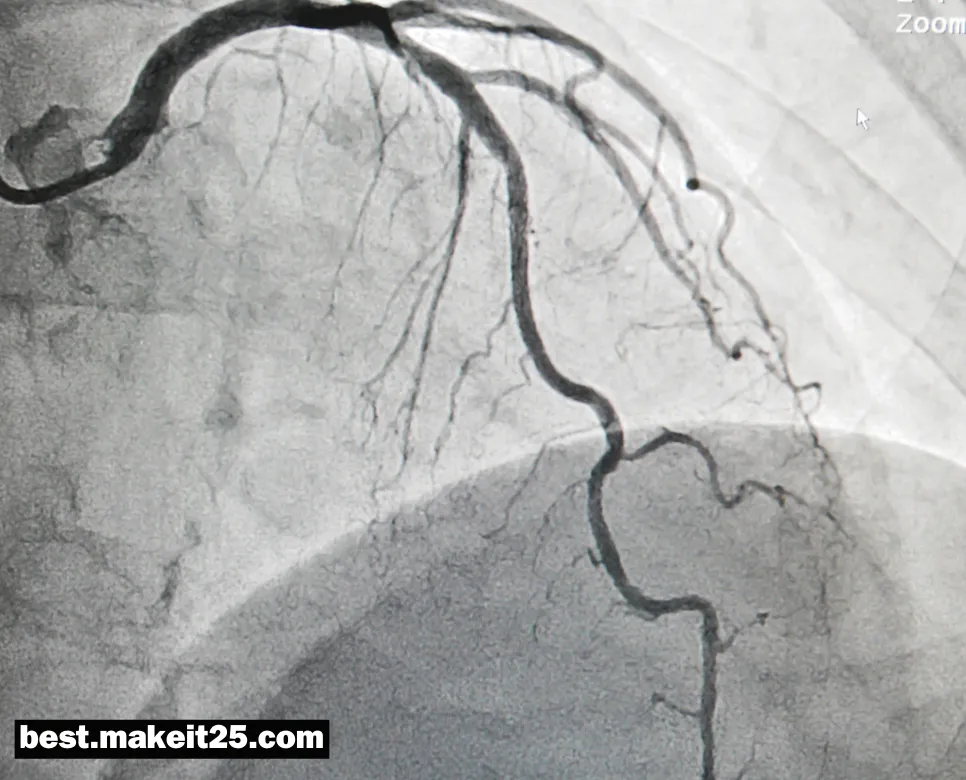

LAD는 의학 용어로 Left Anterior Descending Artery의 약자이며, 한글로는 ‘좌전하행동맥’을 의미합니다. 좌전하행동맥은 좌측 관상동맥의 가장 큰 분지로, 심장의 앞쪽과 좌측 심실의 큰 부분에 혈액을 공급하는 중요한 동맥입니다. 이 동맥은 심장 근육에 산소와 영양분을 공급하는 데 필수적인 역할을 합니다.

• 심근경색과의 연관성: 좌전하행동맥의 폐쇄 또는 심한 협착은 급성 심근경색을 유발할 수 있으며, 특히 ‘Widow Maker’로 알려진 근위부 LAD 병변은 높은 사망률과 관련이 있습니다.

• 관상동맥 조영술: 좌전하행동맥의 협착이나 폐쇄를 진단하기 위해 관상동맥 조영술을 시행합니다.